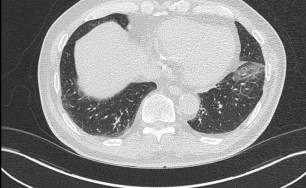

기관지확장증의 CT 사진